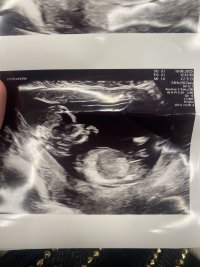

13+5, er dette nub?

Jordmor og nub theory sa man ikke kunne se noe nub, men Earlyglimpse sier dette er gutt og har tatt dette bilde fra videoen jeg sendte.

Baby hadde også navlestrengen mellom beina, så jeg syns det er vanskelig å vite